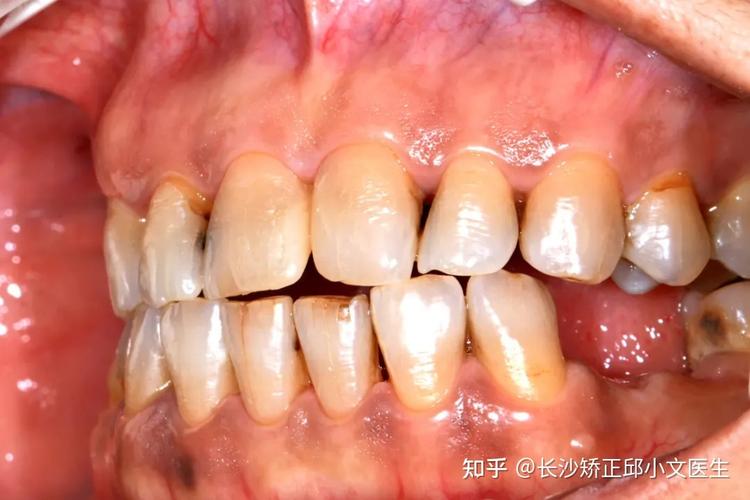

正畸相关的牙龈萎缩通常表现为:牙龈边缘向牙根方向退缩,使牙根部分暴露(暴露程度可能从1-2mm到数毫米不等);牙龈颜色变浅或变暗,质地变薄;暴露的牙根对冷、热、酸、甜刺激敏感,出现酸痛感;严重时可能影响美观,尤其是前牙区牙龈退缩可能导致“牙缝变大”或“牙齿显长”。